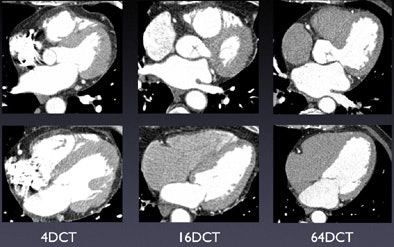

![]() |

| Levocardiograms show continually improving image quality with increased CT detector rows. |